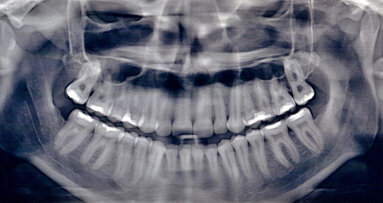

Dvě kazuistiky přímé kompozitní dostavby frontálních zubů s pomocí kompozitního materiálu Charisma Topaz (Heraeus Kulzer). Zkrácená verze – celý článek naleznete na www.stomateam.cz, nebo v časopise StomaTeam 5/2016 (pozn. red.).

Takto velké rekonstrukce funkce frontálních zubů hovoří samy za sebe díky metaanalýze zveřejněné na toto téma, které se podařilo prokázat míru průměrné roční ztráty kompozitních výplní mezi 0 až 4,1 %. Protože hlavním důvodem selhání větších výplní kavit IV. třídy bylo jejich odlomení, je prokázán význam volby stálejších kompozitních materiálů, které mají vysokou pevnost v lomu.